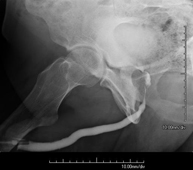

Tècnica que usa els raigs X a través de la qual s'obtenen imatges de l'interior de les extremitats per al seu estudi, especialment dels ossos. Indicacions: traumatisme, infeccions articulars. - RX Artrografia

Procediment que permet, mitjançant l'ús de raigs X, i després d'injectar un contrast a l'interior de l'articulació, detectar lesions d'aquestes articulacions (cartílag, os, tendons, etc. ) segons la distribució del contrast. - RX Pelvis